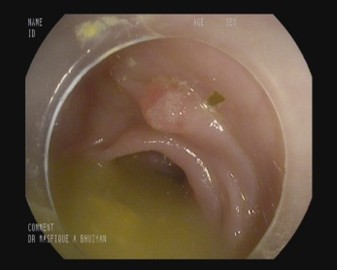

Colonoscopy image datasets are inherently heterogeneous, containing frames acquired under a variety of clinical conditions. As illustrated in Table 4, the data frequently exhibit artifacts that complicate polyp detection and segmentation. Examples include stool residues adhering to the intestinal wall, blood obscuring mucosal surfaces, or inflammation that alters tissue appearance. Additional challenges arise from image acquisition itself, such as low brightness, chromatic aberration, motion blur, or the presence of surgical tools in the field of view.

Table 4: Challenging Polyp image examples of BPD dataset.

Sl. no Image description Image Mask

1 Image containing polyp without any noise or challenging aspects [Uncaptioned image] [Uncaptioned image]

2 Image contains polyp with some stool dotting the intestinal wall [Uncaptioned image] [Uncaptioned image]

3 Image contains polyp with blood being present on the intestine wall [Uncaptioned image] [Uncaptioned image]

4 Image contains polyp in an inflamed intestine [Uncaptioned image] [Uncaptioned image]

5 Blurred or unfocused image containing polyp [Uncaptioned image] [Uncaptioned image]

6 Chromatic aberration distortion present in polyp image [Uncaptioned image] [Uncaptioned image]

7 Low brightness image containing polyp [Uncaptioned image] [Uncaptioned image]

8 Image with improper bowel preparation [Uncaptioned image] [Uncaptioned image]

9 Surgical tool present alongside polyp [Uncaptioned image] [Uncaptioned image]

10 Motion blur present in image [Uncaptioned image] [Uncaptioned image]